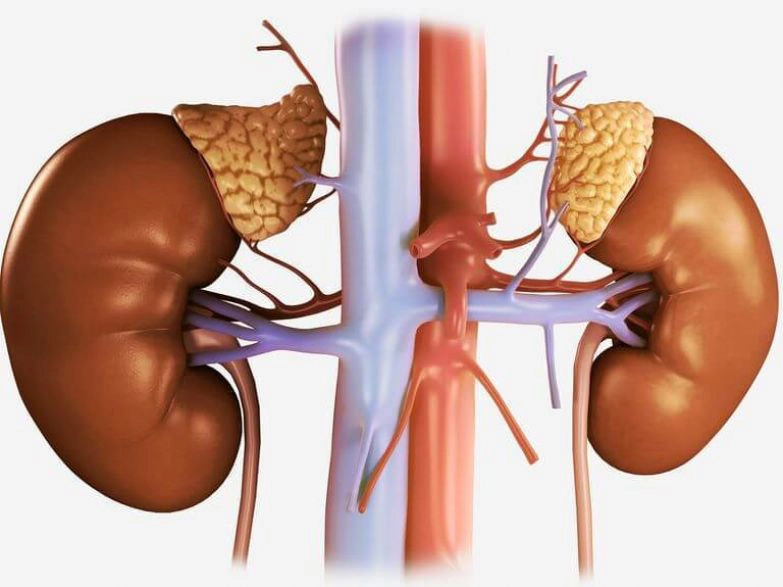

عملکرد کلیه

در طرفین ستون مهره ها و قسمت تحتانی قفسه سینه کلیه قرار دارد. هرکس در حالت طبیعی دارای دو کلیه می باشد. کلیه با عملکرد خود باعث حفظ تعادل در بدن می شود. کلیه دارای وظایفی به شرح ذیل می باشد:

- دفع مواد و مایعات زائد بدن از طریق دفع ادرار

- تصفیه خون

- کمک به حفظ موادی مانند پروتئن در خون

- کنترل بر ایجاد گلبول های قرمز

- تولید ویتامین برای رشد بافت های بدن

- تنظیم هورمون های فشار خون

- کمک به کنترل مواد مغزی شامل کلسیم و پتاسیم

- کمک به تقویت و استحکام استخوان ها